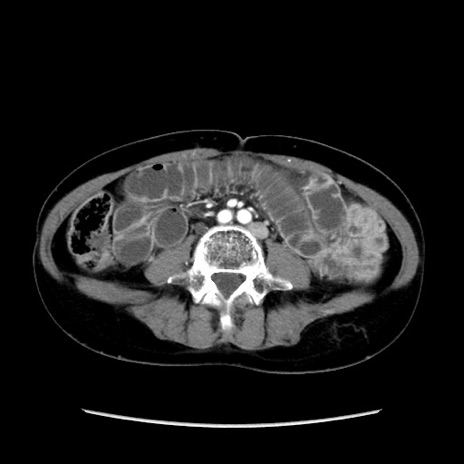

冠状断像

【症例】40歳代 女性

【主訴】上腹部痛、嘔気・嘔吐

【現病歴】約9時間前頃から急に上腹部痛、嘔気、嘔吐が出現。改善しないため救急要請。

【既往歴】子宮頚癌(広汎子宮全摘術、放射線療法)、腸閉塞

【身体所見】腹部:平坦、軟、腸雑音亢進、上腹部を中心に腹部全体に圧痛あり。

【データ】WBC 8400、CRP 0.03